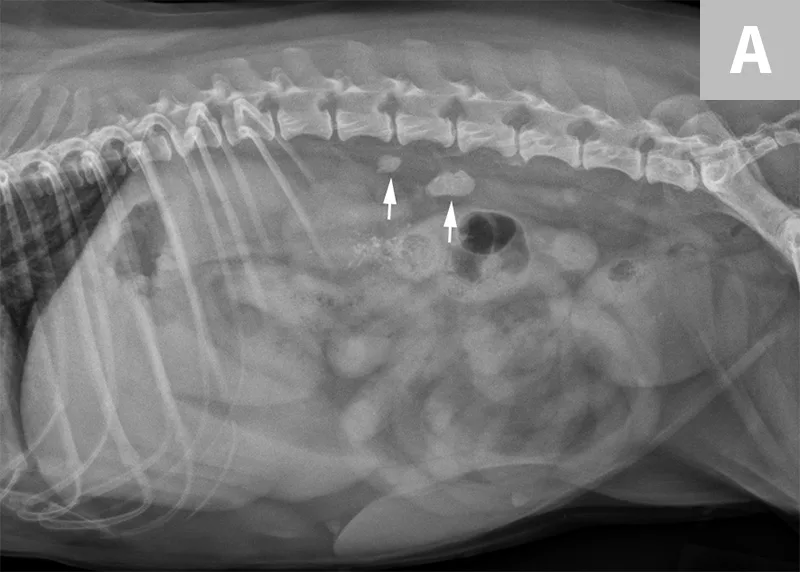

Lateral abdominal radiograph of a dog with 2 well-defined, oval mineral opacities superimposed over the retroperitoneal space caudal and dorsal to the kidneys (arrows). Based on the ventrodorsal projection (not shown), these calculi were likely to be associated with the right ureter.

Ureteral calculi are a common cause of ureteral obstruction; localization of ureteral calculi is imperative prior to choosing appropriate management. While ureteral calculi have been reported as the most common cause of ureteral obstructions, other causes such as iatrogenic ligation, blood clots, tumor, strictures (congenital and acquired), solidified blood stones, and a circumcaval ureter have been reported.4-7

The obstruction can be located at any point of the ureter and can vary in severity. Normal ureters are typically not seen on ultrasonography due to their small size. The easiest way to locate a dilated ureter is to trace the ureter from the renal pelvis. In most cases, the ureter is dilated proximal to the site of an obstruction and tapers to a more normal appearance distal to the site of obstruction. Imaging can also reveal retroperitoneal effusion which can result from ureteritis and possible urine leakage.